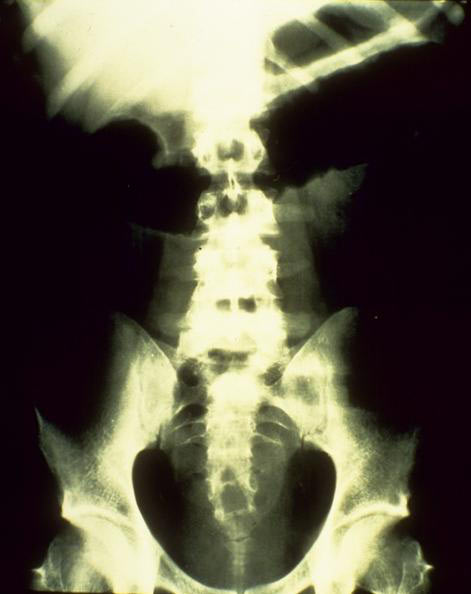

das toxische Megacolon (=vor einer entzündlichen Verschwellung der Darmlichtung im S-Darm oder an der haarnadelförmigen linken Flexur kommt es zu einer Stauung des Darminhaltes mit massiver Aufweitung der Darmschlinge: in schweren Fällen platzt (perforiert) der Darm und es bildet sich eine gefährliche Bauchhöhlenentzündung); » A45